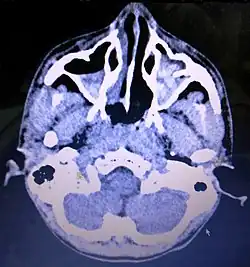

Cancer

Carcinoma of the maxillary sinus may invade the palate and cause dental pain. It may also block the nasolacrimal duct. Spread of the tumor into the orbit causes proptosis.[1]

-

Maxillary sinus cancer that has spread to the brain -

Maxillary sinus cancer that has spread to the lymph nodes